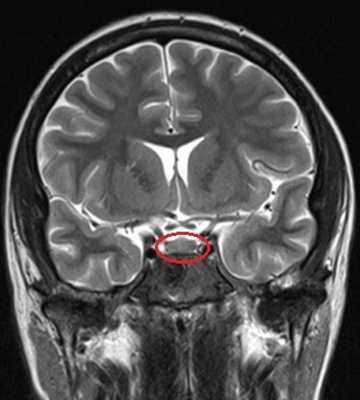

МРТ гипофиза (обведено) без контраста и с с контрастом. В норме гипофиз равномерно накапливает контрастное вещество — становится светлым.

МРТ гипофиза с контрастом и без: А- гипофиз нормальных размеров (обведено кругом), В - симметричные кальцификации (стрелки)